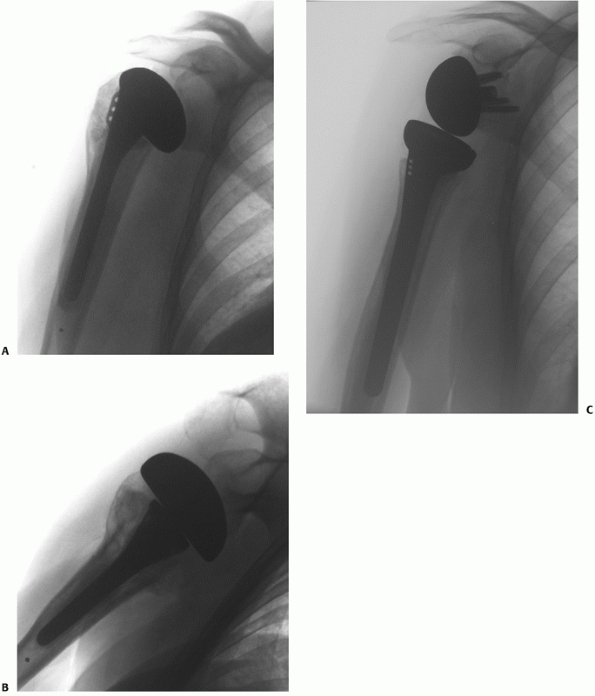

torsional redisplacement of the shaft from the head and to provide

additional fixation of reduced tuberosity fragments. This technique is

the most widely used method to treat displaced but salvageable two-,

three-, and four-part fractures. Several key steps are identified,

which are critical to the success of the reconstruction.

The procedure can be performed through a deltopectoral or extended

deltoid-splitting approach, identifying and protecting the anterior

branch of the axillary nerve before any fracture manipulation or

instrumentation. In three-part greater tuberosity and four-part

fractures, the main split in the tuberosities is first located in the

area immediately posterior to the bicipital groove. The space formed by